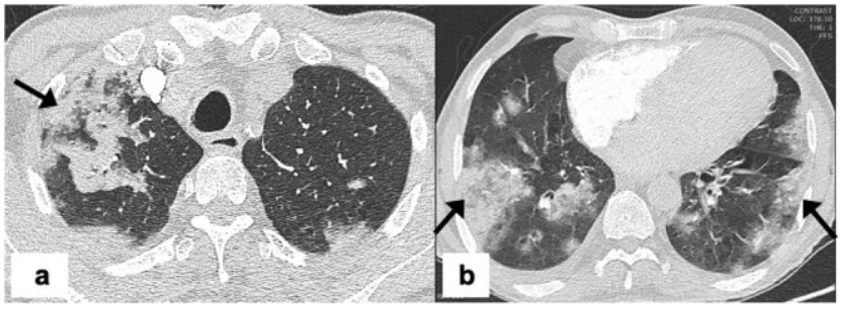

肺隔离症:易误诊为肺癌的占位性病变,肺穿刺禁忌!

肺段与肺内管道应用解剖  肺转移瘤的十种不典型CT表现

肺转移瘤的十种不典型CT表现  肺内淋巴结的CT表现特点及与病理对照